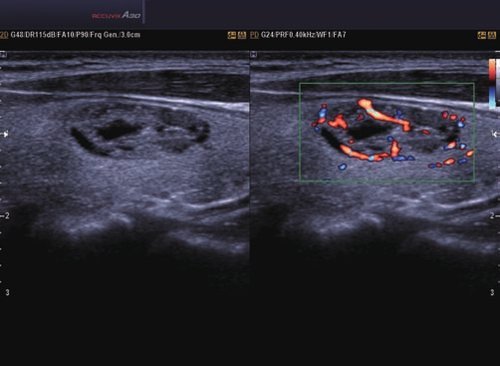

• Farb-Doppler

• Power-Doppler (PD)

• Directional Power Doppler (DPD)

• Color Opt Flow™ bietet kraftvollere Farben und verbessert die Bildqualität.